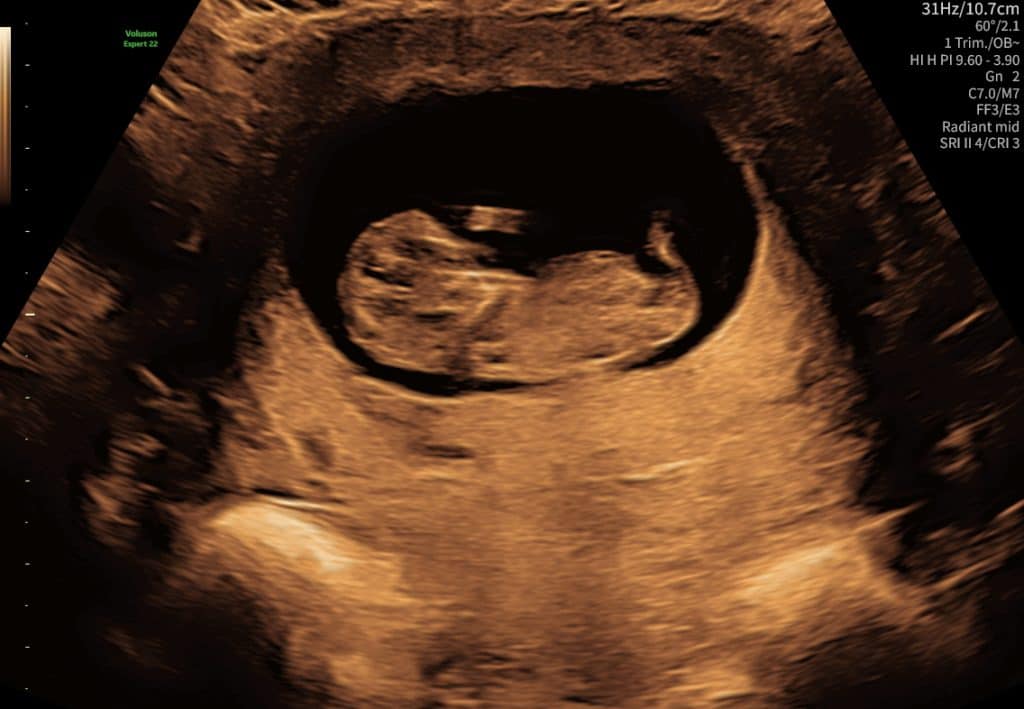

Ultralydsscanning uge 10 foster med hoved og krop

Ultralydsscanning uge 9 foster

Ultralyd i uge 9–10. Fosteret er mere tydeligt, men detaljer kan stadig variere.

I denne periode er der flere bevægelser som ofte ses tydeligere på video end på stillbilleder.

Kort ultralydssekvens fra uge 10 hvor foster kan ses i profil med hjerte som slår. Meget livlig